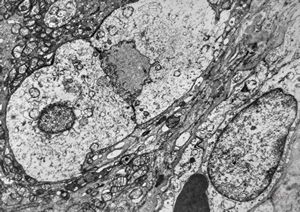

F,49y. | purulent meningitis- meningococcal v.s.